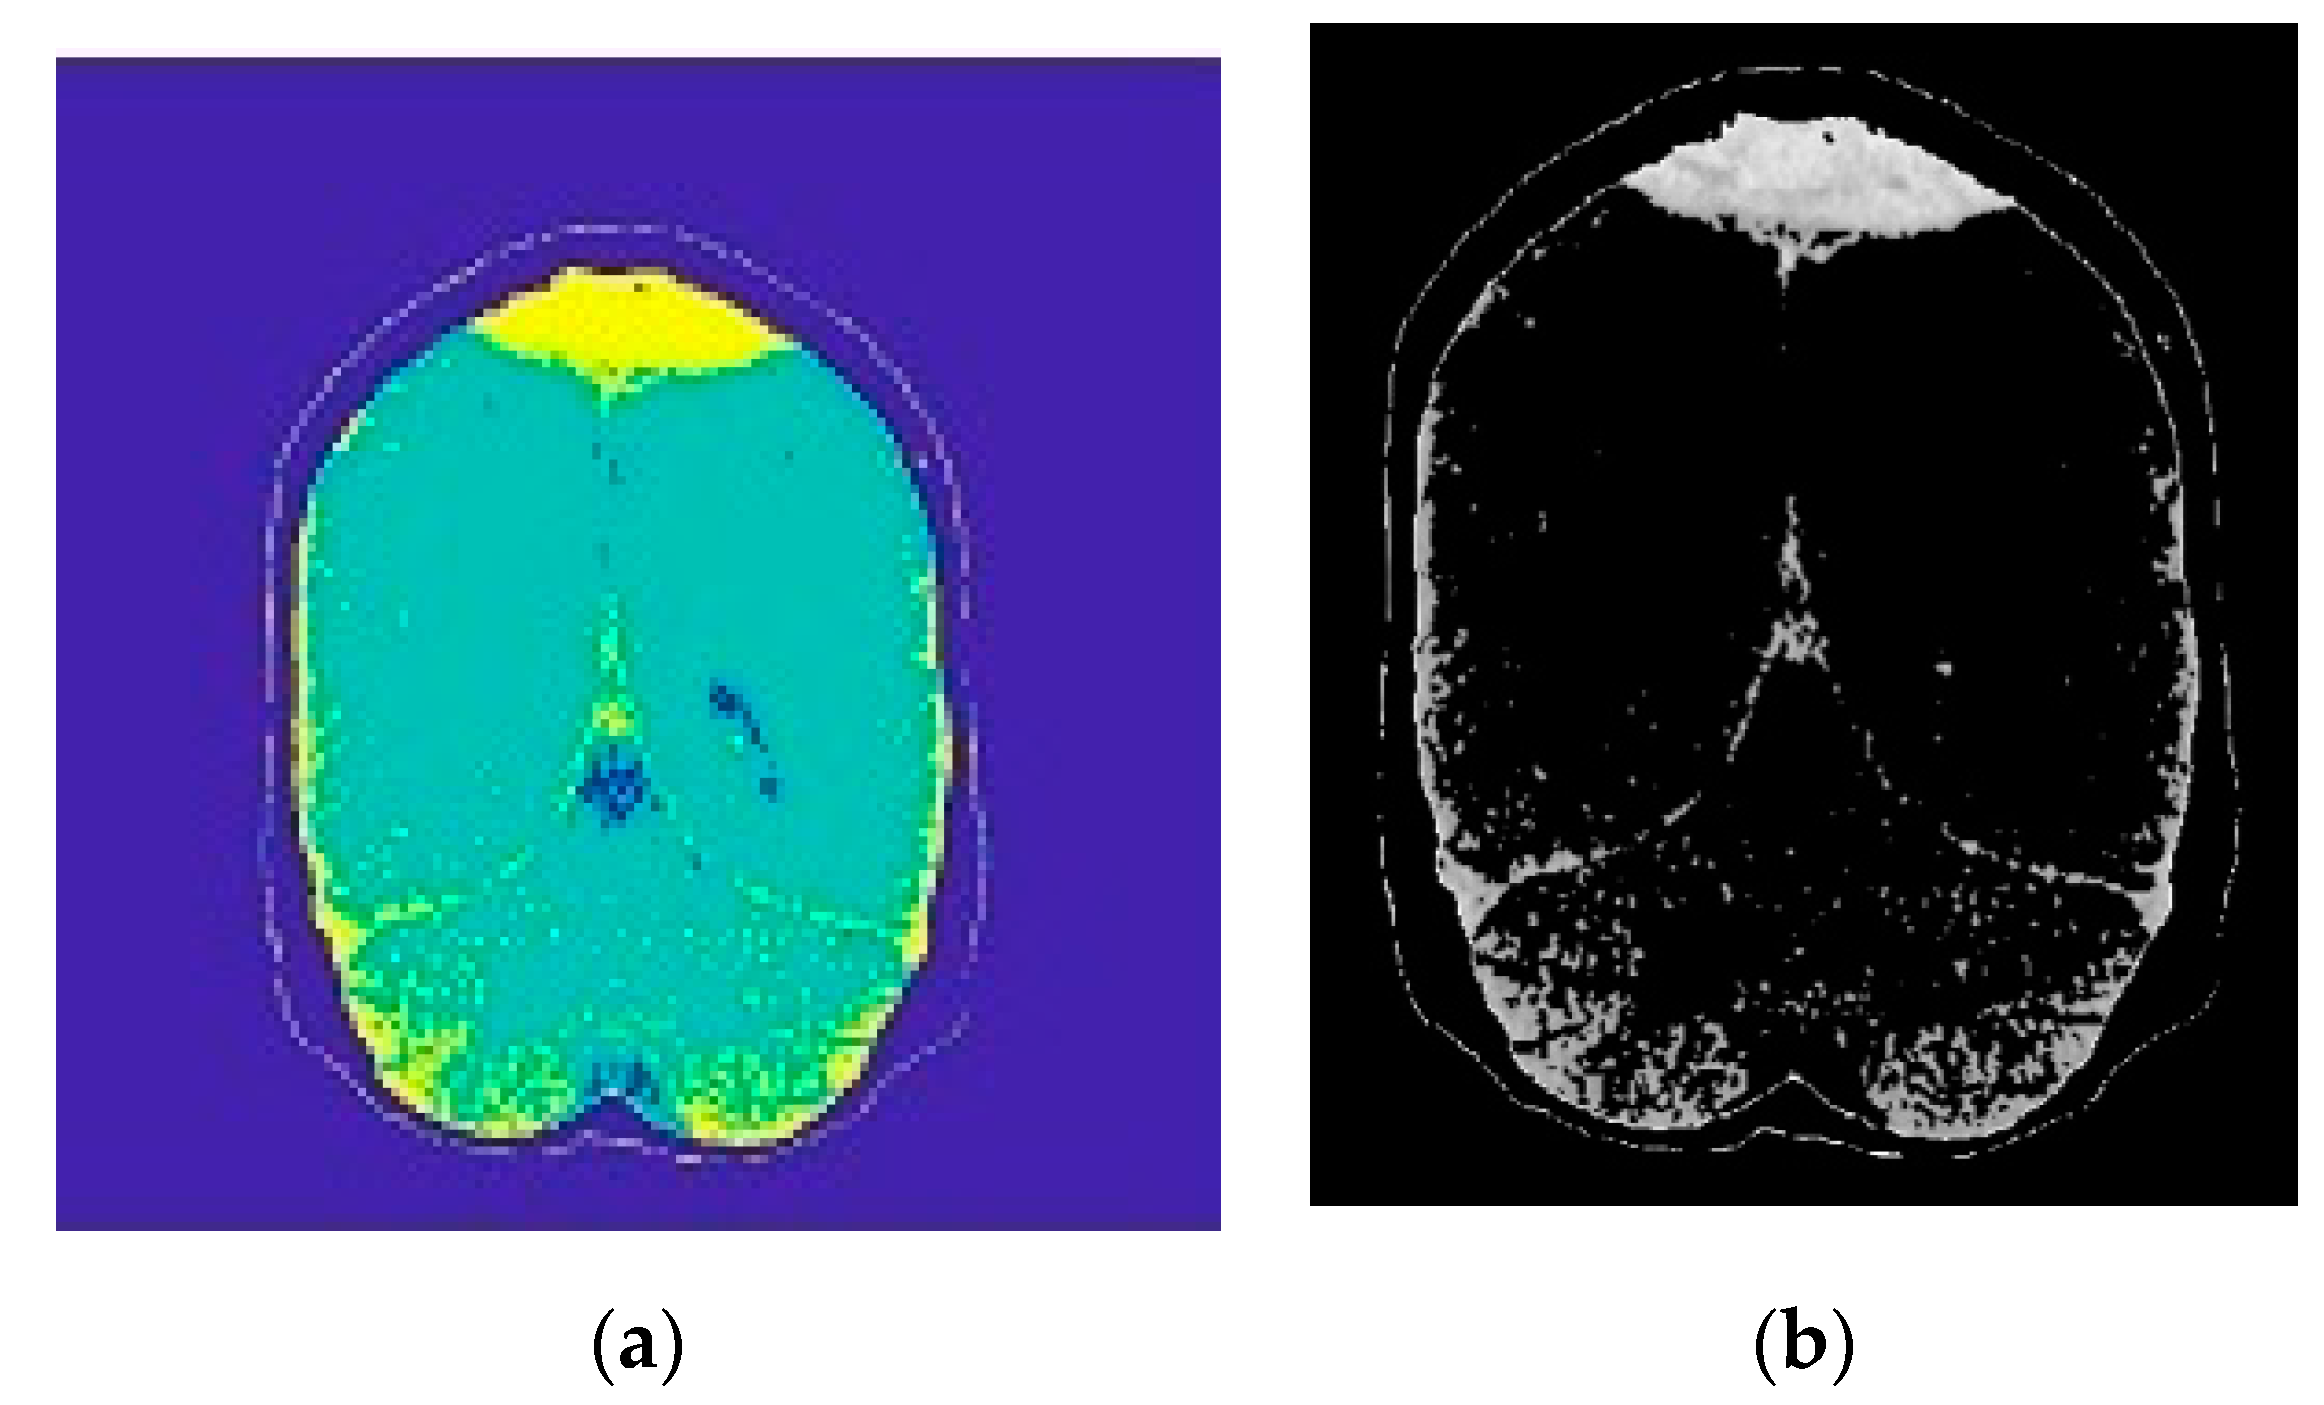

2.2.1. Image Segmentation

2.2.2. Morphological Operations